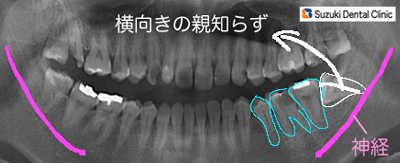

(抜歯前)親知らずの歯だけが斜めに生えています=写真左。